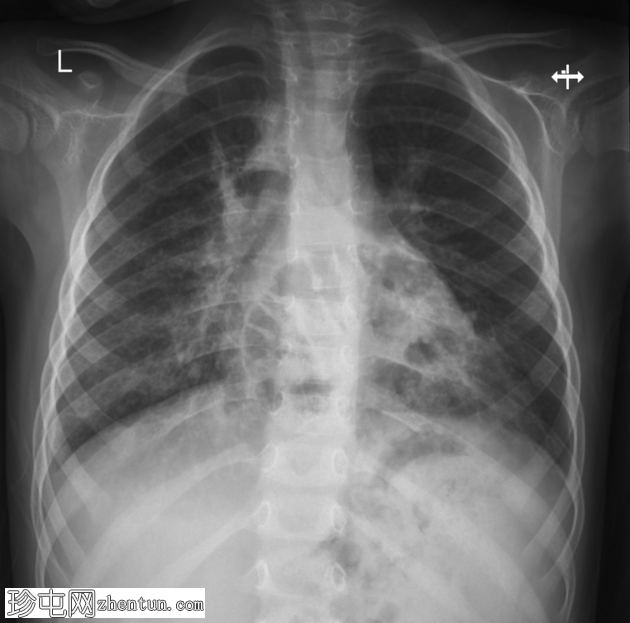

X线片

1.png

正位片

底部可见边界不清的阴影,最符合呼吸道感染的表现。

正位和侧位片上偶然发现胸骨后肠管。